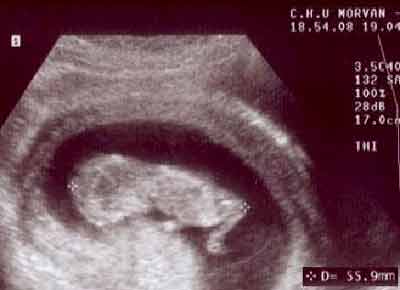

Embryon en extension